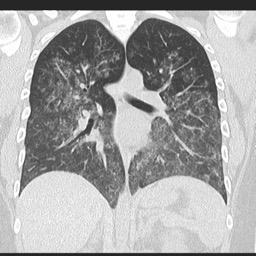

o HRCT: Opacități difuze în sticlă mată și consolidare alveolară.

Hemoragie alveolară difuză datorată vasculitei

Sursa: radiopaedia.org